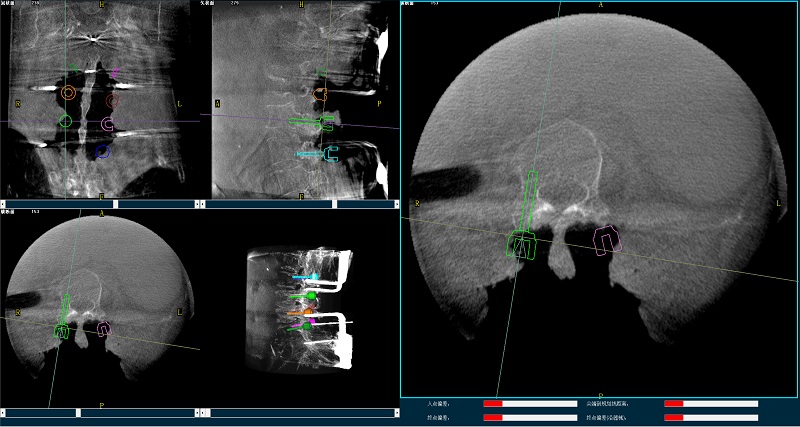

手術規劃圖像

(4)在骨科機器人導航系統輔助下,一次性準確植入8枚椎弓根螺釘。